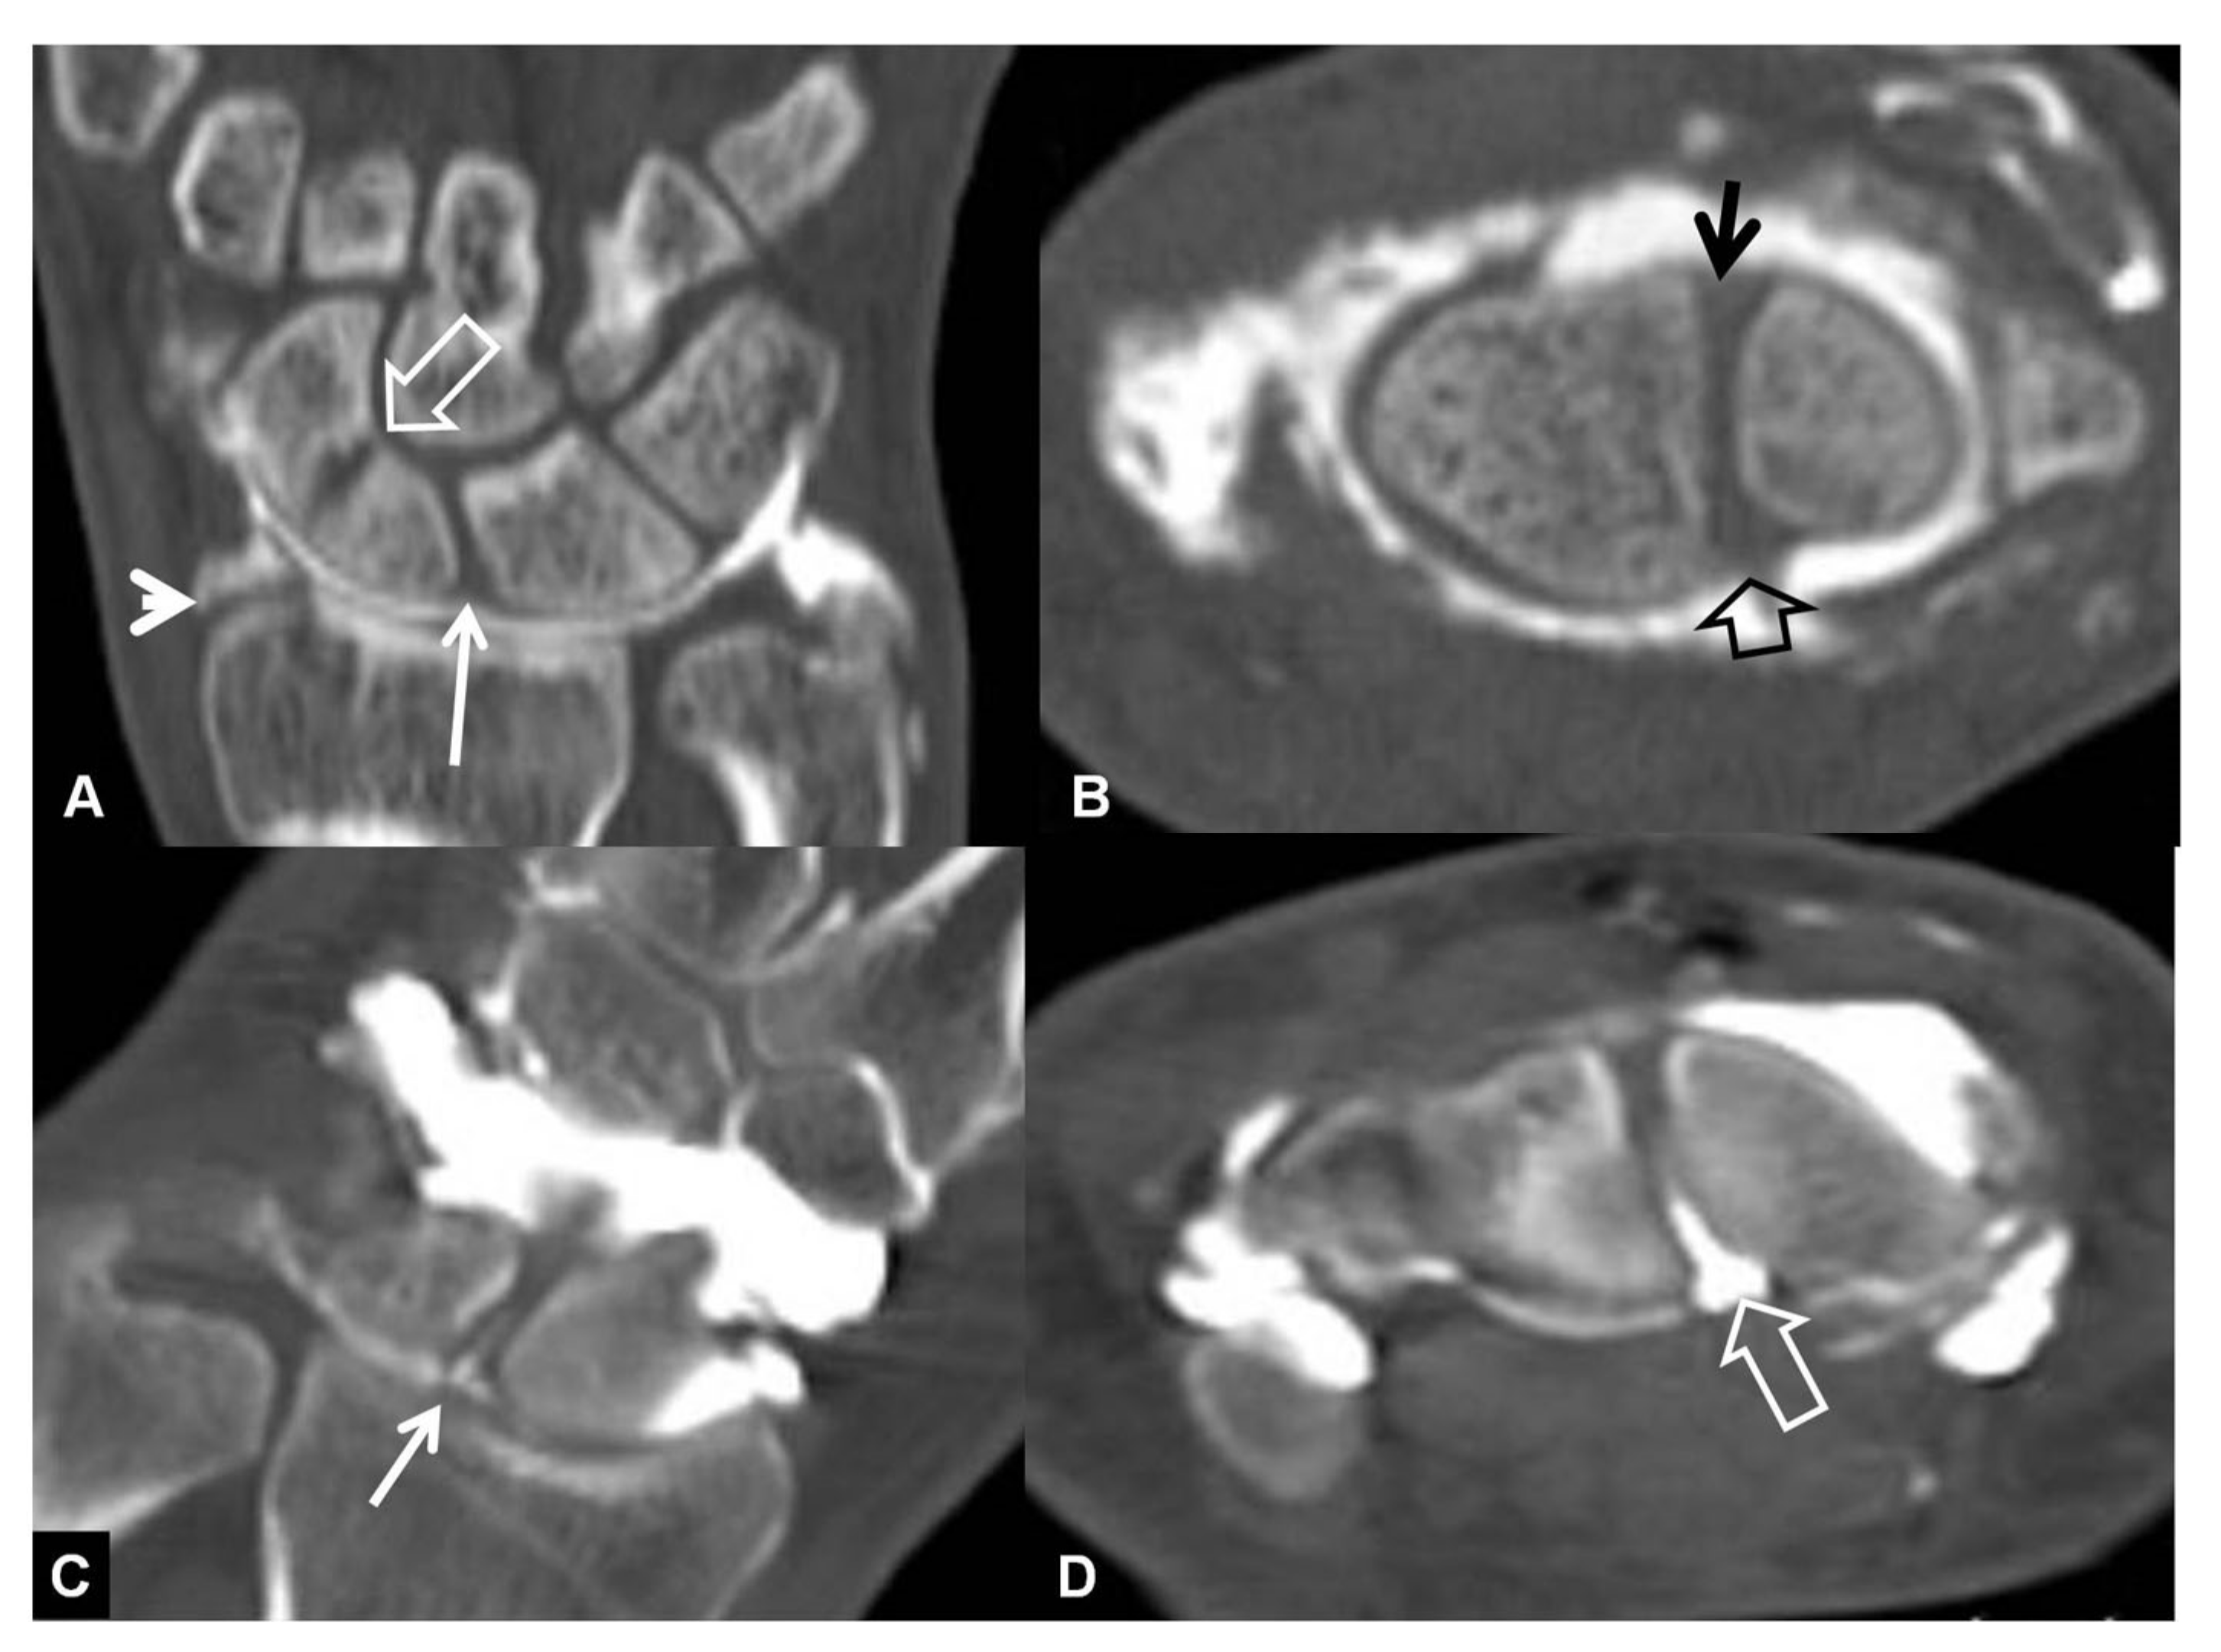

CT-arthrography (CTa) is performed with an iodine contrast material injected in specific wrist joints. For depicting a SLL tear, a single injection at the radioscaphoid joint is performed in our department under fluoroscopic or ultrasound guidance. In the presence of a tear, the midcarpal joints will be opacified (Figure 8).

Figure 8.

A 33-year-old with a history of scaphoid fracture. (A) Coronal CT-arthrographic image showing the scaphoid pseudarthrosis (open arrow), a radial styloid process fracture (arrowhead) and an intact scapholunate ligament (arrow). (B) Axial CT-arthrographic image showing the intact dorsal (arrow) and palmar (open arrow) parts of the scapholunate ligament. A 56-year-old male patient who was involved in a motor vehicle accident 1 year prior to current imaging. Coronal (C) and axial (D) CT-arthrographic images showing a tear at the membranous (arrow) and palmar (open arrow) parts of the scapholunate ligament.